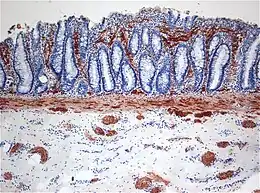

Histopathology of Hirschsprung disease showing abnormal acetylcholine esterase (AchE)-positive nerve fibers (brown) in the mucosa